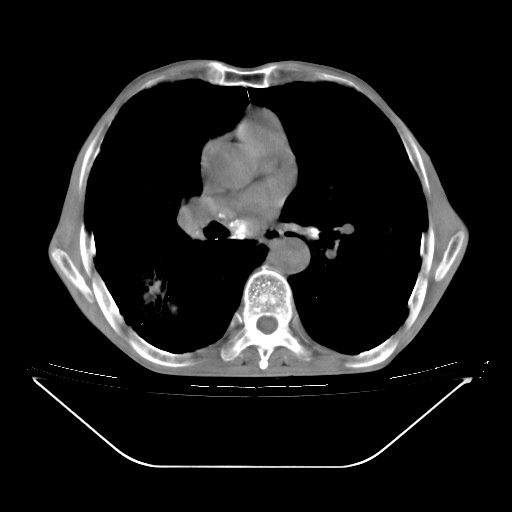

以下是引用zsl6918在2008-8-25 21:55:00的发言:[br]符合右肺周围性肺癌并肺内转移,左肺结核球。双肺肺气肿。腰椎附件转移。

以下是引用随光逐影在2008-8-25 22:03:00的发言:[br]1)考虑右肺下叶周围性肺癌并肺内转移,腰椎附件转移。2)左上肺结核(结核球形成)。3)双肺肺气肿(多发肺大泡形成)。4)双肺门区及纵隔内多发淋巴结钙化。